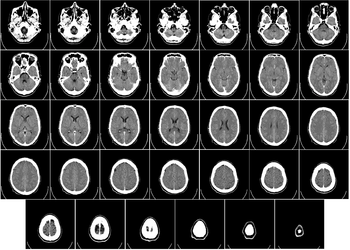

Head

CT scanning of the head is typically used to detect infarction, tumors, calcifications, haemorrhage and bone trauma. Of the above, hypodense (dark) structures can indicate edema and infarction, hyperdense (bright) structures indicate calcifications and haemorrhage and bone trauma can be seen as disjunction in bone windows. Tumors can be detected by the swelling and anatomical distortion they cause, or by surrounding edema. Ambulances equipped with small bore multi-sliced CT scanners respond to cases involving stroke or head trauma. CT scanning of the head is also used in CT-guided stereotactic surgery and radiosurgery for treatment of intracranial tumors, arteriovenous malformations and other surgically treatable conditions using a device known as the N-localizer.[12][13][14][15][16][17]

Magnetic resonance imaging (MRI) of the head provides superior information as compared to CT scans when seeking information about headache to confirm a diagnosis of neoplasm, vascular disease, posterior cranial fossa lesions, cervicomedullary lesions, or intracranial pressure disorders.[18] It also does not carry the risks of exposing the patient to ionizing radiation.[18] CT scans may be used to diagnose headache when neuroimaging is indicated and MRI is not available, or in emergency settings when hemorrhage, stroke, or traumatic brain injury are suspected.[18] Even in emergency situations, when a head injury is minor as determined by a physician's evaluation and based on established guidelines, CT of the head should be avoided for adults and delayed pending clinical observation in the emergency department for children.[19]